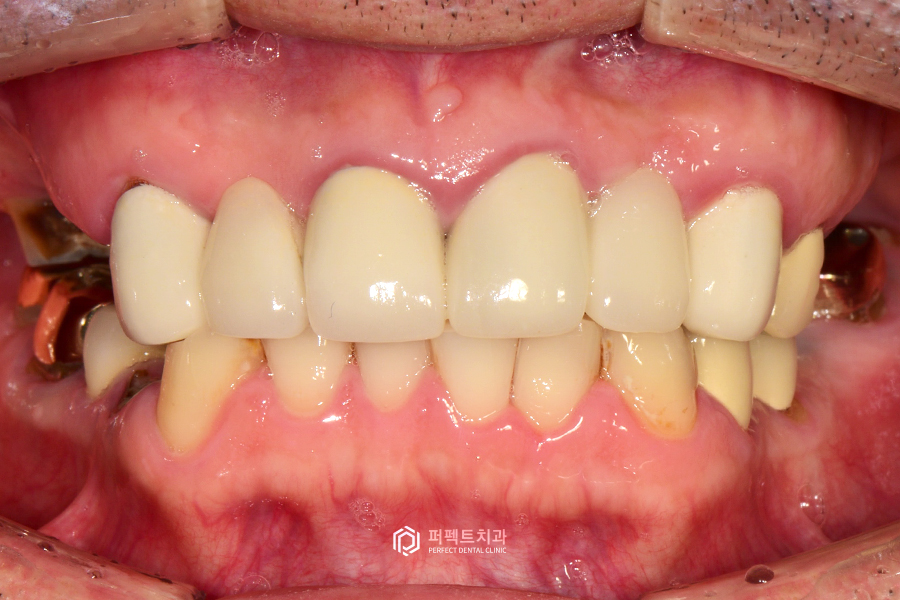

정면 사진을 보시면 기존에 했던 보철물보다 좀 더 자연스러운 색깔을 원하셔서 위 아래와 비슷한 색상을 진행을 했습니다.

상악 사진을 보시면 뿌리만 남은 치아들과 치아가 없는 부분들을 임플란트로 수복하고, 앞니 보철까지 교체를 해서 윗니 전악 보철 케이스가 된 경우입니다.

치아가 없는 부분은 임플란트로, 기존 보철물은 지르코니아 크라운으로 교체를 해서 윗니는 전체적으로 치아가 다시 완성된 케이스라고 생각을 하시면 될 것 같습니다.